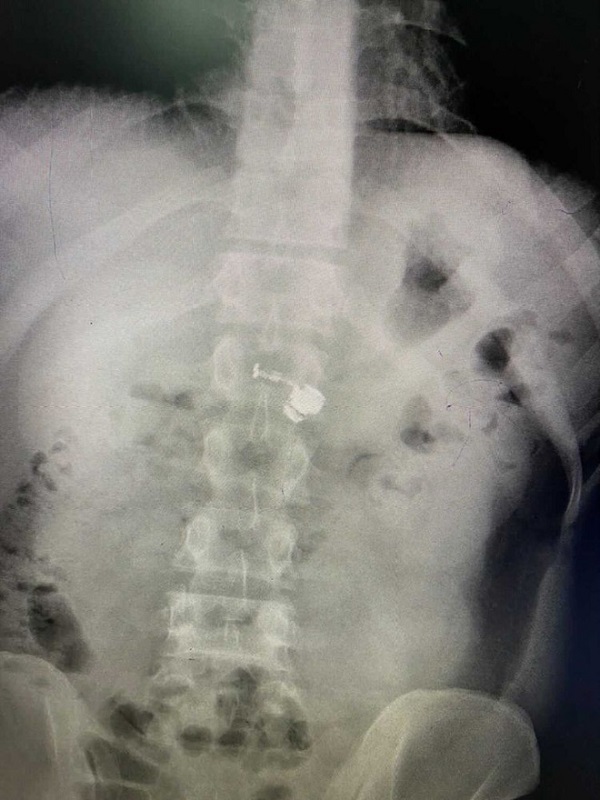

Các bác sĩ đã yêu cầu ông đi chụp X-quang. Sau khi có kết quả, bác sĩ đã nói thông tin khiến ông Gauthier bị sốc. Một chiếc tai nghe AirPod không dây đã mắc kẹt trong thực quản của ông. Các bác sĩ tin rằng ông đã vô tình nuốt phải khi đang ngủ.

Vị trí tai nghe mắc kẹt trong thực quản không gây tổn thương hay bất kỳ hậu quả gì nghiêm trọng. Bác sĩ đã thực hiện nội soi và dễ dàng lấy tai nghe ra ngoài. Ngay sau nội soi, ông Gauthier đã xuất viện về nhà, theo New York Post.